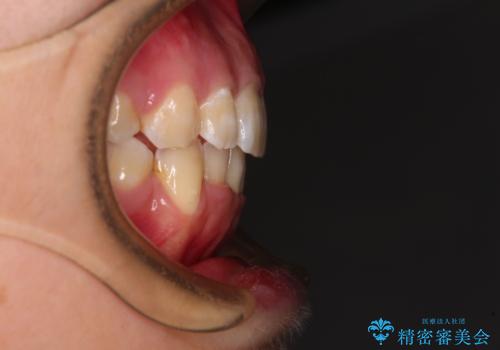

前歯の出っ歯と口の閉じにくさを抜歯矯正で改善 目立たないワイヤー矯正

4本の歯を抜歯したことで、飛び出していた口元が引っ込み、横顔が大きく改善されました。